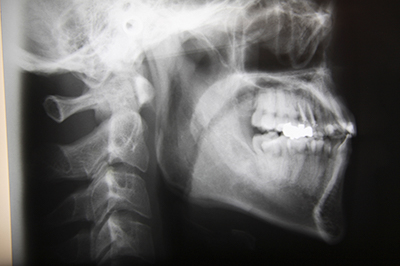

歯科口腔外科とは

お口の中をのぞいて見えるすべての組織、つまり歯や歯茎だけでなく、舌、頬の粘膜、舌の付け根、上顎、下顎、唇と、粘膜に隠れている唾液腺(つばを出す組織)、さらに顔や顎の形をつくっている骨、顎関節など、これらに生じた病気やけがを専門に診断、治療する診療科が歯科口腔外科です。

埋伏歯 親知らずがうずく、痛いといった症状。歯科でレントゲンを撮ったら親知らずが埋まっていると指摘されることが多い。またはなかなか永久歯が生えてこない、など。

顎関節症 口が大きく開かない、顎を動かすとカクカク音がする。痛みがあるなど。